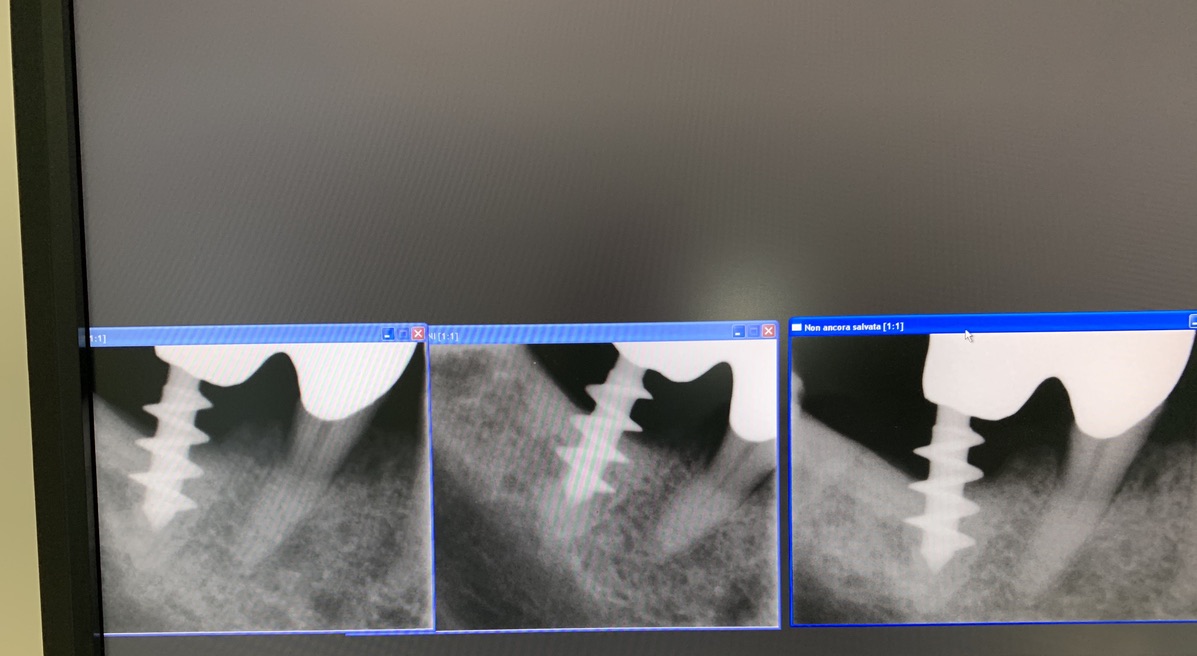

Forma originale dell’impianto di Tramonte. Diametro 5 mm a 3 spire. Gambo diam. 2,1 mm. Collo diam.2 mm x 5 mm di lunghezza. Titanio di grado 2. Il grado 2 consentiva al bisogno di piegare il collo dell’impianto per migliorare il parallelismo. Si tratta di un impianto postestrattivo immediato. Perciò nella stessa seduta estrazione, alesatura maschiatura ed inserimento dell’impianto. Subito seguiti da monconizzazione e da confezione di corone provvisorie in occlusione leggera. Le radiografie fornite evidenziano la situazione a partire dal 2010. La emergenza del collo sottile favorisce la formazione di un manicotto di gengiva densa che protegge dalle periimplantiti. Le spire larghe irradiano lontano dal corpo impianto il carico occlusale favorendo la formazione di un osso più omogeneo.